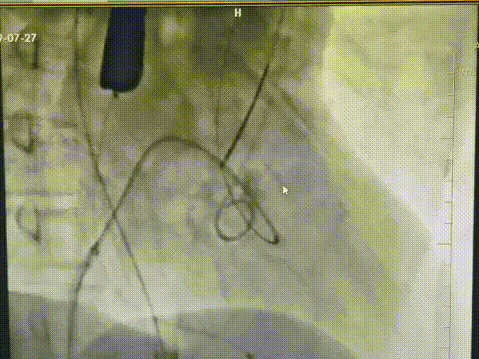

7. 退出球囊,圈套器协助下沿导丝成功将TAV 27mm VitaFlow®瓣膜支架系统送达主动脉瓣狭窄处;

8. 定位满意后起搏150bpm缓慢释放支架系统;

9. 复查造影:瓣膜支架系统膨胀,位置良好,沿导丝将一枚22mm*40mm的VitaFlow®瓣膜球囊扩张导管送至瓣膜支架系统内,定位后扩张瓣膜支架。

经猪尾导管复查造影:瓣膜支架系统膨胀良好,未见瓣周漏,冠脉显影正常,食道超声提示瓣膜工作正常,压差解除,无瓣周漏。